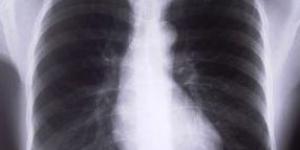

La pleuresia es una inflamación de la pleura, es decir, de la membrana serosa que recubre los pulmones y se repliega sobre todos los órganos contenidos en el tórax y entre sus lóbulos.Se trata de una inflamación que puede ser causada por traumatismos en el tórax, alteraciones costillares o debido a la...